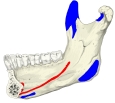

起始部より内側下方に走る。

The two mylohyoid muscles arise from the mandible at the mylohyoid line, which extends from the mandibular symphysis in front to the last molar tooth behind. The posterior fibers pass inferomedially and insert at anterior surface of the hyoid bone. The medial fibres of the two mylohyoid muscles unite in a midline raphe (where two muscles intermesh).[1] :987-8